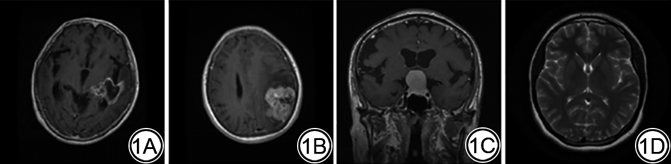

相比其他领域的数据,头部肿瘤病例的MRI数据更难获取,数据量也较少。本文使用两个公开的数据集的组合,对头部MRI图像进行肿瘤的四分类。第一个是Kaggle的500张正常无肿瘤脑部MRI图片(https://github.com/sartajbhuvaji/brain-tumor-classification-dataset);第二个是Figshare数据集(https://figshare.com/articles/dataset/brain_tumor_dataset/1512427),该数据集来自2005年至2010年间中国广州南方医院和天津医科大学总医院,包含了233名匿名癌症患者的3064张脑肿瘤MRI图片。经临床专业人员进行人工归类,所有MRI图片都有标签,作为有监督网络训练时的参考。其中脑膜瘤708张、胶质瘤1426张、垂体瘤930张,四类代表性MRI图像如图1所示。采用的两个数据集均遵守《赫尔辛基宣言》,我们的任务就是对这四种MRI图像进行分类。